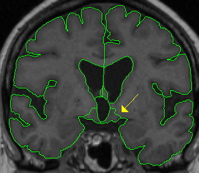

| General Description The ventral diencephalon (VDC) is not an anatomical name for a single structure but a name we've given to a group of structures that generally cannot be distinguished from each other with standard MRI images. This "miscellaneous" area includes the hypothalamus, mammillary body, subthalamic nuclei, substantia nigra, red nucleus, lateral geniculate nucleus (LGN), and medial geniculate nucleus (MGN). White matter areas such as the zona incerta, cerebral peduncle (crus cerebri), lenticular fasciculus, and the medial lemniscus are also included in this area. The optic tract is included in this area in the most anterior extent. Each structure fades in and out of the VDC at different times. Therefore, the VDC greatly varies from slice to slic | |

|  | Part I - Anterior portion of VDC The anterior VDC starts one slice posterior to the anterior commisure and should be defined by an isointensity contour line. The superior border is the hypothalamic fissure and the thalamus. This contour should exclude the anterior commissure, fornix, or any surrounding white matter and by convention should extend only a little wider than the optic chiasm (when present). The VDC should never extend to the pallidum. |

|  | Part II - Thalamus appears In most cases the same contour line used for the thalamus will work for the lateral borders of the VDC. The contour line should provide most of the lateral border of the VCD, though some manual editing with the draw function may be required. If the best fit contour shows the internal capsule, or cerebral peduncle cutting dramatically into the VDC manually edit the contour to include that portion of the internal capsule, or cerebral peduncle in the volume of the VDC. |

|  | The LGN may have to be drawn in manually or defined by a separate contour. The choroidal fissure is the inferior border of the LGN. The most posterior extent of the VDC is the LGN, therefore when the LGN is gone there is no more VDC. |

| Labeling This outline is labeled "VentralDC." | |